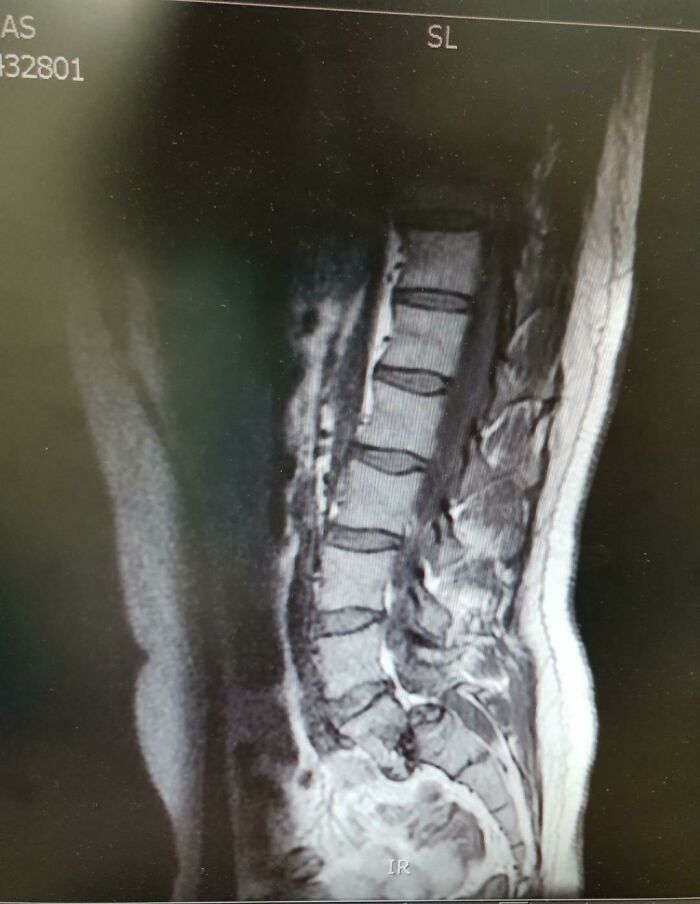

#67 I Was Diagnosed With Spondylolisthesis, A Condition Where A Vertebrae Moves Out Of Position. Managed To Run A 10k At 55mins While My Lower Back Looked Like This